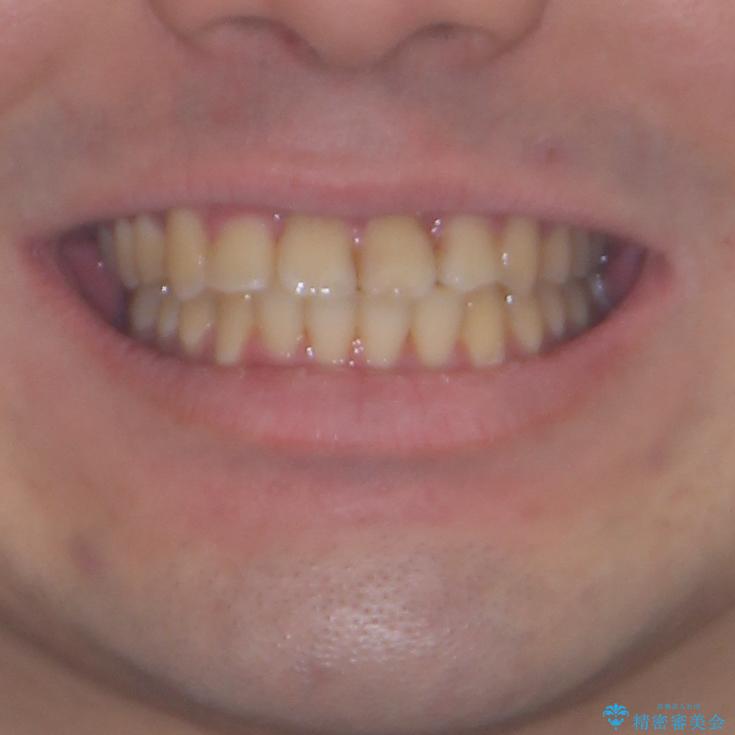

歯列全体のクロスバイトを治したい ワイヤー装置による矯正治療

- 上下のデコボコと前歯のクロスバイトを改善したいとのことで来院された患者様です。

マウスピース矯正での自己管理には自信がないとのことで、ワイヤー装置による矯正治療を行うこととしました。

デコボコの程度は強かったのですが、口元の突出感はなかったため、非抜歯矯正としました。